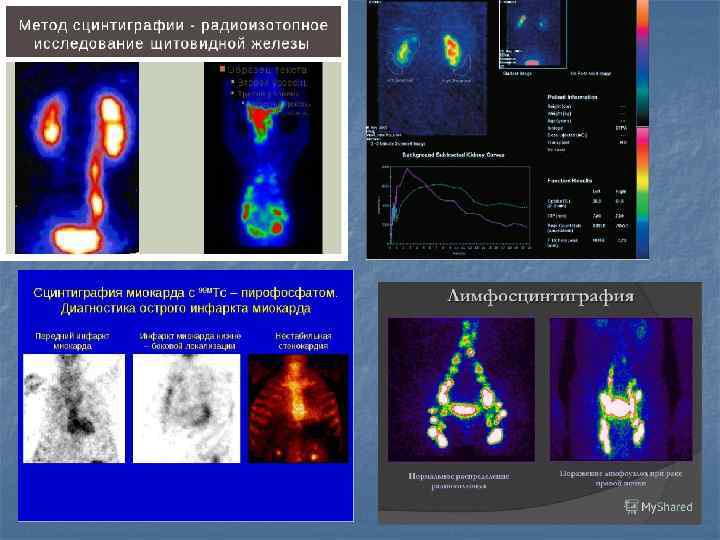

Показания n n n n Диагностика ишемической болезни сердца (ИБС) в том числе путём выявления преходящей ишемии миокарда, рубцовых изменений, исследования сократительной способности сердца. Диагностика тромбоэмболии лёгочной артерии. Диагностика метастазов и первичных опухолей костной ткани, переломов, воспаления, и инфекций (остеосцинтиграфия). Исследование кровоснабжения головного мозга — используется в диагностике болезни Альцгеймера, некоторых форм деменции, инфекционных заболеваний. Существуют маркеры, позволяющие проследить распределение рецепторов некоторых нейромедиаторов в ткани мозга, например, дофамина, что можно использовать в диагностике болезни Паркинсона. Диагностика заболеваний щитовидной и паращитовидной желез. Оценка функции почек и их кровоснабжения. Выявление заболеваний печени, функциональных расстройств гепатобилиарной системы.